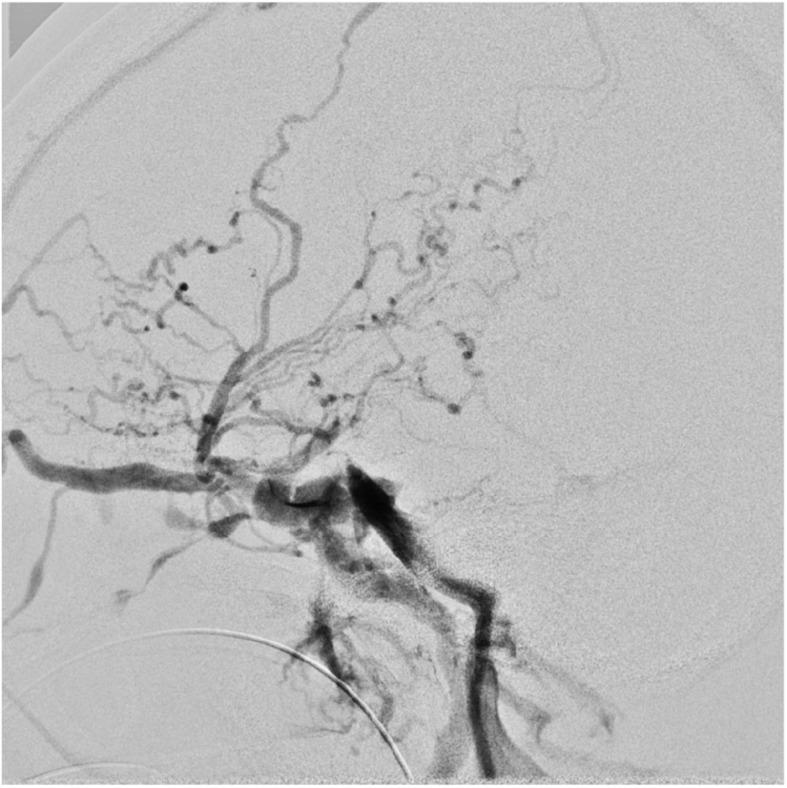

We experienced a case of difficult catheterization to the left brachiocephalic vein (LBCV) during transfemoral transvenous embolization for traumatic carotid-cavernous fistula. We discussed the cause of this phenomenon.

CASE PRESENTATION

A 78-year-old woman with a traumatic carotid-cavernous fistula was treated with combined transarterial and transvenous embolization; however, catheterization to the LBCV was very difficult. A balloon guiding catheter (BGC) already placed in the left common carotid artery (LCCA) caused displacement of the LCCA and further compression of the originally stenotic LBCV.A CT investigation of 104 cases of neuroendovascular treatment in our hospital revealed that the distance between the ventral bones and the dorsal arteries sandwiching the LBCV was significantly negatively correlated with age (r = -0.41, p = 0.000020). Aging and arteriosclerotic change are possibly related to the LBCV stenosis.

CONCLUSION

When catheterization to the LBCV is difficult during transfemoral transvenous embolization, not only the presence of anatomical variations and stenosis or occlusion of LBCV itself but also compression from surrounding structures should be considered, especially in elderly patients. In rare cases, a catheter inserted in an adjacent artery may cause further compression of the LBCV.

我们在经股静脉栓塞治疗外伤性颈内动脉海绵窦瘘的过程中遇到了一例难以将导管插入左头臂静脉(LBCV)的情况。我们对这一现象的原因进行了讨论。

病例介绍

一名78岁患有外伤性颈内动脉海绵窦瘘的女性接受了经动脉和经静脉联合栓塞治疗;然而,将导管插入LBCV非常困难。已置于左颈总动脉(LCCA)的球囊引导导管(BGC)导致LCCA移位,并进一步压迫原本就狭窄的LBCV。对我院104例神经血管内治疗病例的CT研究显示,夹着LBCV的腹侧骨骼与背侧动脉之间的距离与年龄呈显著负相关(r = -0.41,p = 0.000020)。衰老和动脉硬化改变可能与LBCV狭窄有关。

结论

在经股静脉栓塞过程中,当难以将导管插入LBCV时,不仅应考虑LBCV本身存在解剖变异、狭窄或闭塞的情况,还应考虑周围结构的压迫,尤其是在老年患者中。在罕见情况下,插入相邻动脉的导管可能会导致LBCV进一步受压。